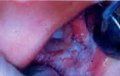

引起急性壞死性潰瘍性口腔病變,本病為急性感染性炎症,本病多見於18~30歲的年輕人。牙齦邊緣及齦乳頭頂端出現壞死,下前牙唇側多見。牙齦邊緣呈“蟲蝕狀”,牙齦乳頭消失變平如“刀削狀”。在壞死組織表面可有灰白色的假膜形成,容易擦去,擦去後可見出血的創面。唇、頰、舌、齶、咽、口底等處黏膜均可受累,形成不規則形狀的壞死性深潰瘍,上覆灰黃或灰黑色假膜,周圍黏膜有明顯的充血水腫,觸之易出血。疼痛明顯,常伴有流涎、發熱、頭痛、淋巴結腫等症狀。急性期未及時治療,壞死就會向鄰近的口腔黏膜及深層組織蔓延,在全身抵抗力急劇下降,同時合併產氣莢膜桿菌感染時,還可造成面頰的洞穿性缺損,稱為走馬疳或面頰壞疽。大量的毒性產物可導致患者的死亡。急性期治療不徹底或反覆發作,遷延不愈還可轉變為慢性。牙齦乳頭破壞嚴重,牙齦失去正常外形,齦緣呈反波浪形。嚴重者可造成牙槽骨吸收,牙周袋形成。發病急驟,症狀顯著,有發熱、全身不適以及頜下淋巴結腫大。潰瘍好發於牙齦和頰黏膜,形態不定,大小多在1cm左右,表淺,披以污穢的、灰白色苔膜,擦去此苔膜時,出現溢血的潰瘍面,但不久又再被覆以同樣的苔膜,周圍黏膜有明顯充血水腫,觸痛明顯,並有特彆強烈的壞死組織臭味。此病確診的依據為特殊性口臭,苔膜與小潰瘍,塗片中找到大量梭形桿菌與奮森螺鏇體。

2.牙齦邊緣及齦乳頭頂端出現壞死,受累黏膜形成不規則形狀的壞死性深潰瘍,上覆灰黃或灰黑色假膜。